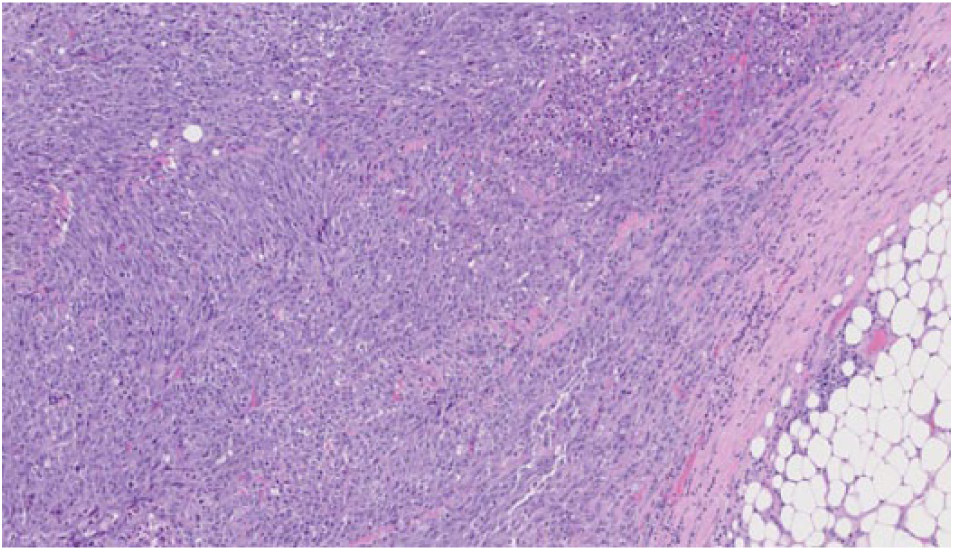

The microscopic examination of the kidney tumor revealed sheets of atypical spindle cells with abnormal mitotic figures, nuclear pleomorphism, and areas of necrosis compatible with sRCC (Figure 3) with osseous metaplasia (Figure 4). The tumor disrupted the renal capsule and extended to the posterior tissue resection edge. A hilar lymph node was positive for metastatic carcinoma. The metastatic tumor showed papillary architecture with abundant eosinophilic cytoplasm, high-grade nuclei, prominent nucleoli with necrosis, and psammoma bodies consistent with type 2 (eosinophilic) PRCC (Figure 5). The RCC tumor thrombus and venous and lymphatic invasion were identified. Ureterovascular margins were negative for malignancy. The adrenal gland, spleen, pancreas, and bowel were also negative for malignancy.

Sarcomatoid spindle cells.